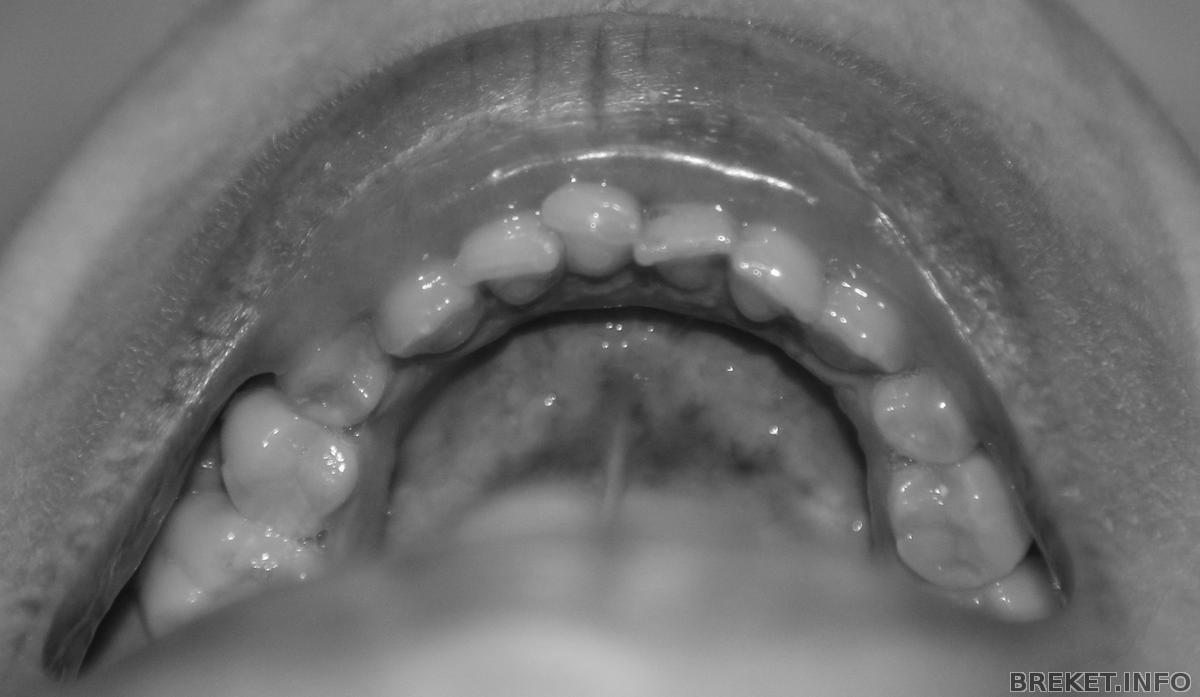

Вот, выношу на ваш суд свои зубки:

img_5347b.jpg